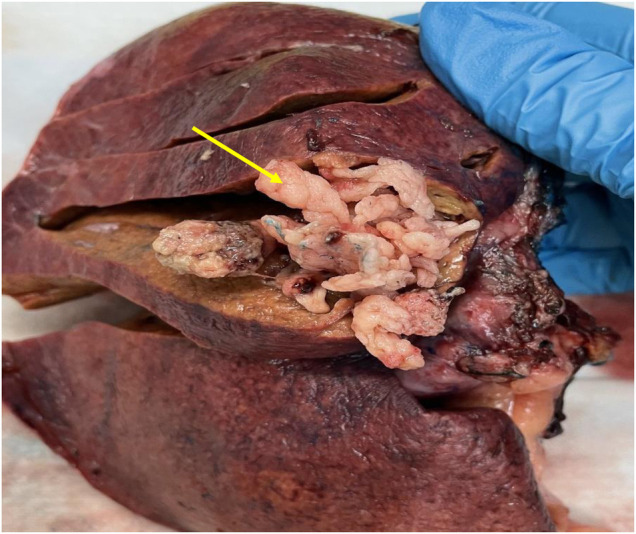

A 65-year-old male Caucasian with a history of multiple comorbid conditions presented to the emergency room with complaints of moderate constant pain at the right upper quadrant (RUQ) abdomen for the last several hours. Differential diagnoses of symptomatic cholelithiasis, cholangitis, and liver abscess were entertained. On physical examination, he was found to have normal vital signs, with icteric sclera and pain on deep palpation at the RUQ region. Upper abdominal ultrasonography (U/S) (Figure 1A) revealed a 6 cm heterogeneous mass in the left hepatic lobe and dilated gall bladder with mild sludge or stones. His laboratory results were significant for elevated liver enzymes, bilirubin and creatinine, hyperglycemia, and leukocytosis (Table 1). Subsequently, he had a hepatobiliary (HPB) iminodiacetic acid scan, which showed no excretion of hepatobiliary radionuclide related to either severe liver dysfunction or high-grade biliary obstruction. In addition, a computed tomography (CT) scan of the upper abdomen and pelvis (Figure 1B) was performed, which confirmed the U/S findings of the lesion in the left lobe of the liver and demonstrated areas of internal enhancement, and magnetic resonance cholangiopancreatography (MRCP) (Figures 1C,D) revealed mild gall bladder wall edema and a 9 mm common bile duct (CBD) dilatation of without evidence of choledocholithiasis, and it was consistent with an undetermined 5 cm mass in the left lobe of the liver. To confirm the pathology of the lesion, the referring physician performed a CT-guided biopsy, which revealed an intrahepatic papillary mucinous neoplasm. This case was discussed at the HPB multidisciplinary conference, and the patient was recommended to undergo left liver mass resection, cholecystectomy, and repair of incisional hernia. His comorbid conditions include cardiac disease, chronic obstructive pulmonary disease, diabetes mellitus, hypertension, and cerebrovascular accident. Cardiology evaluated the patient and declared him as a moderate surgical risk. He uneventfully underwent robotic left partial liver resection, cholecystectomy, lymphadenectomy, and repair of ventral hernia, and his hospital course was unremarkable. Gross pathology (Figure 2A) and histology (Figures 2B,C) revealed negative margins, and the 4.5 cm × 3.5 cm × 3.0 cm cystic structure from hepatic tissue represents the intrahepatic biliary IPMN (yellow arrow) (Figure 3) with low-grade dysplasia. The central aspect of the mass is comprised of pink-tan papillary tissue. There is no gross evidence of invasion (Figure 3). The remainder of the liver parenchyma is red-brown and firm. The patient came for regular postoperative follow-up and is still alive. The lesion had low-grade dysplasia and no malignant focus; however, the patient still underwent abdominal ultrasound after 3 months and a CT scan after 1 year. Also, he was followed up by his primary care doctor. His last visit to a hospital was on 20 March 2023 for non-IPMN or non–liver-related issues. He had a history of cerebro vascular accident (CVA) with dense right hemiparesis. His postoperative course was uneventful, other than a mild urinary tract infection for which he was prescribed antibiotics. He progressed well with physical therapy and was discharged to an inpatient rehab after 8 days of hospital stay. The patient had an extended stay at the hospital due to a lack of rehab beds. He was readmitted to the hospital from rehab due to a pulseless electrical activity (PEA) cardiac arrest for a short period, from which he successfully recovered and was discharged home with an outpatient rehab plan.